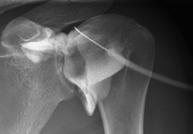

- Pelvis X-ray

This procedure uses X-ray imaging to examine the pelvis, especially the pelvic bones.